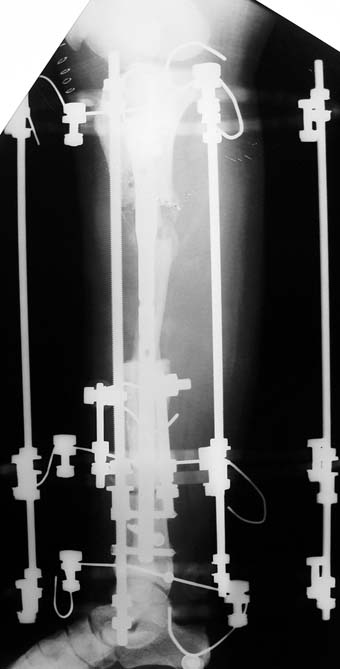

Uygun radikal debridman tüm nekrotik kemik ve yumuşak dokuların çıkartılmasını gerektirir, ve sıklıkla uzuvda instabiliteye neden olur. Kalan kemik ve yumuşak doku defektinin bir şekilde fiksasyonu ve rekonstrüksiyonu gereklidir. İlizarov’un ortaya koyduğu distraksiyon osteogenezi yöntemi, kaynamanın elde edilmesi, deformitenin düzeltilmesi, bacak boy eşitsizliğinin giderilmesi ve segmental defektlerin rekonstrükte edilmesi için başarıyla kullanılmaktadır.

Eksternal fiksatör ile geçen süre (eksternal fiksasyon indeksi), gereken distraksiyon miktarına bağlıdır ve bu süre boyunca bazı komplikasyonlarla karşılaşılabilir. Distraksiyon dönemi sona erdikten sonra, distraksiyon süresinin iki katını aşan konsolidasyon döneminde hastalar eksternal fiksatörü zorlukla tolere edebilirler. Yeterli konsolidasyon sağlanmadan eksternal fiksatör çıkartılırsa ise kırıklar, deformite ve kısalık oluşabilir. Hastanın fiksatör ile birlikte geçirdiği sürenin azaltılması ve böylece hasta konforunun ve aktivite düzeyinin arttırılması için intramedüller çivi üzerinden uzatma yöntemi uygulanmaktadır. Bu yöntemde distraksiyon dönemi sona erdiğinde kemiğin içindeki çivi statik olarak kilitlenmekte ve eksternal fiksatör çıkartılmaktadır. Stabilizasyon intramedüller çivi tarafından sağlandıktan sonra konsolidasyon dönemi gerçekleşmektedir. Bu şekilde hem eksternal fiksatörün uzun süre kalmasından hem de erken çıkartılmasından kaynaklanan komplikasyonların önüne geçilmektedir.